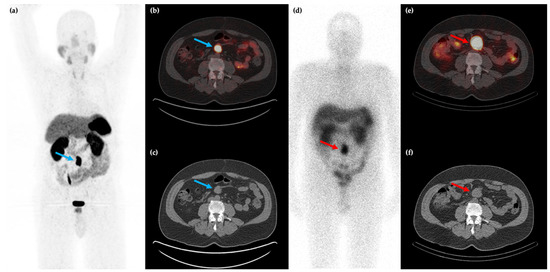

Figure 1.

58-year-old male with a history of rectal bleeding and a mesenteric mass identified on conventional CT imaging. 68Ga-DOTATATE PET/CT maximum intensity projection (MIP) (a) and axial (b,c) images shows the somatostatin receptor (SSTR) positive lesion at the root of the small bowel mesentery (blue arrows) with improved spatial resolution compared to 111In-pentreotide SPECT/CT ((d–f), red arrows).